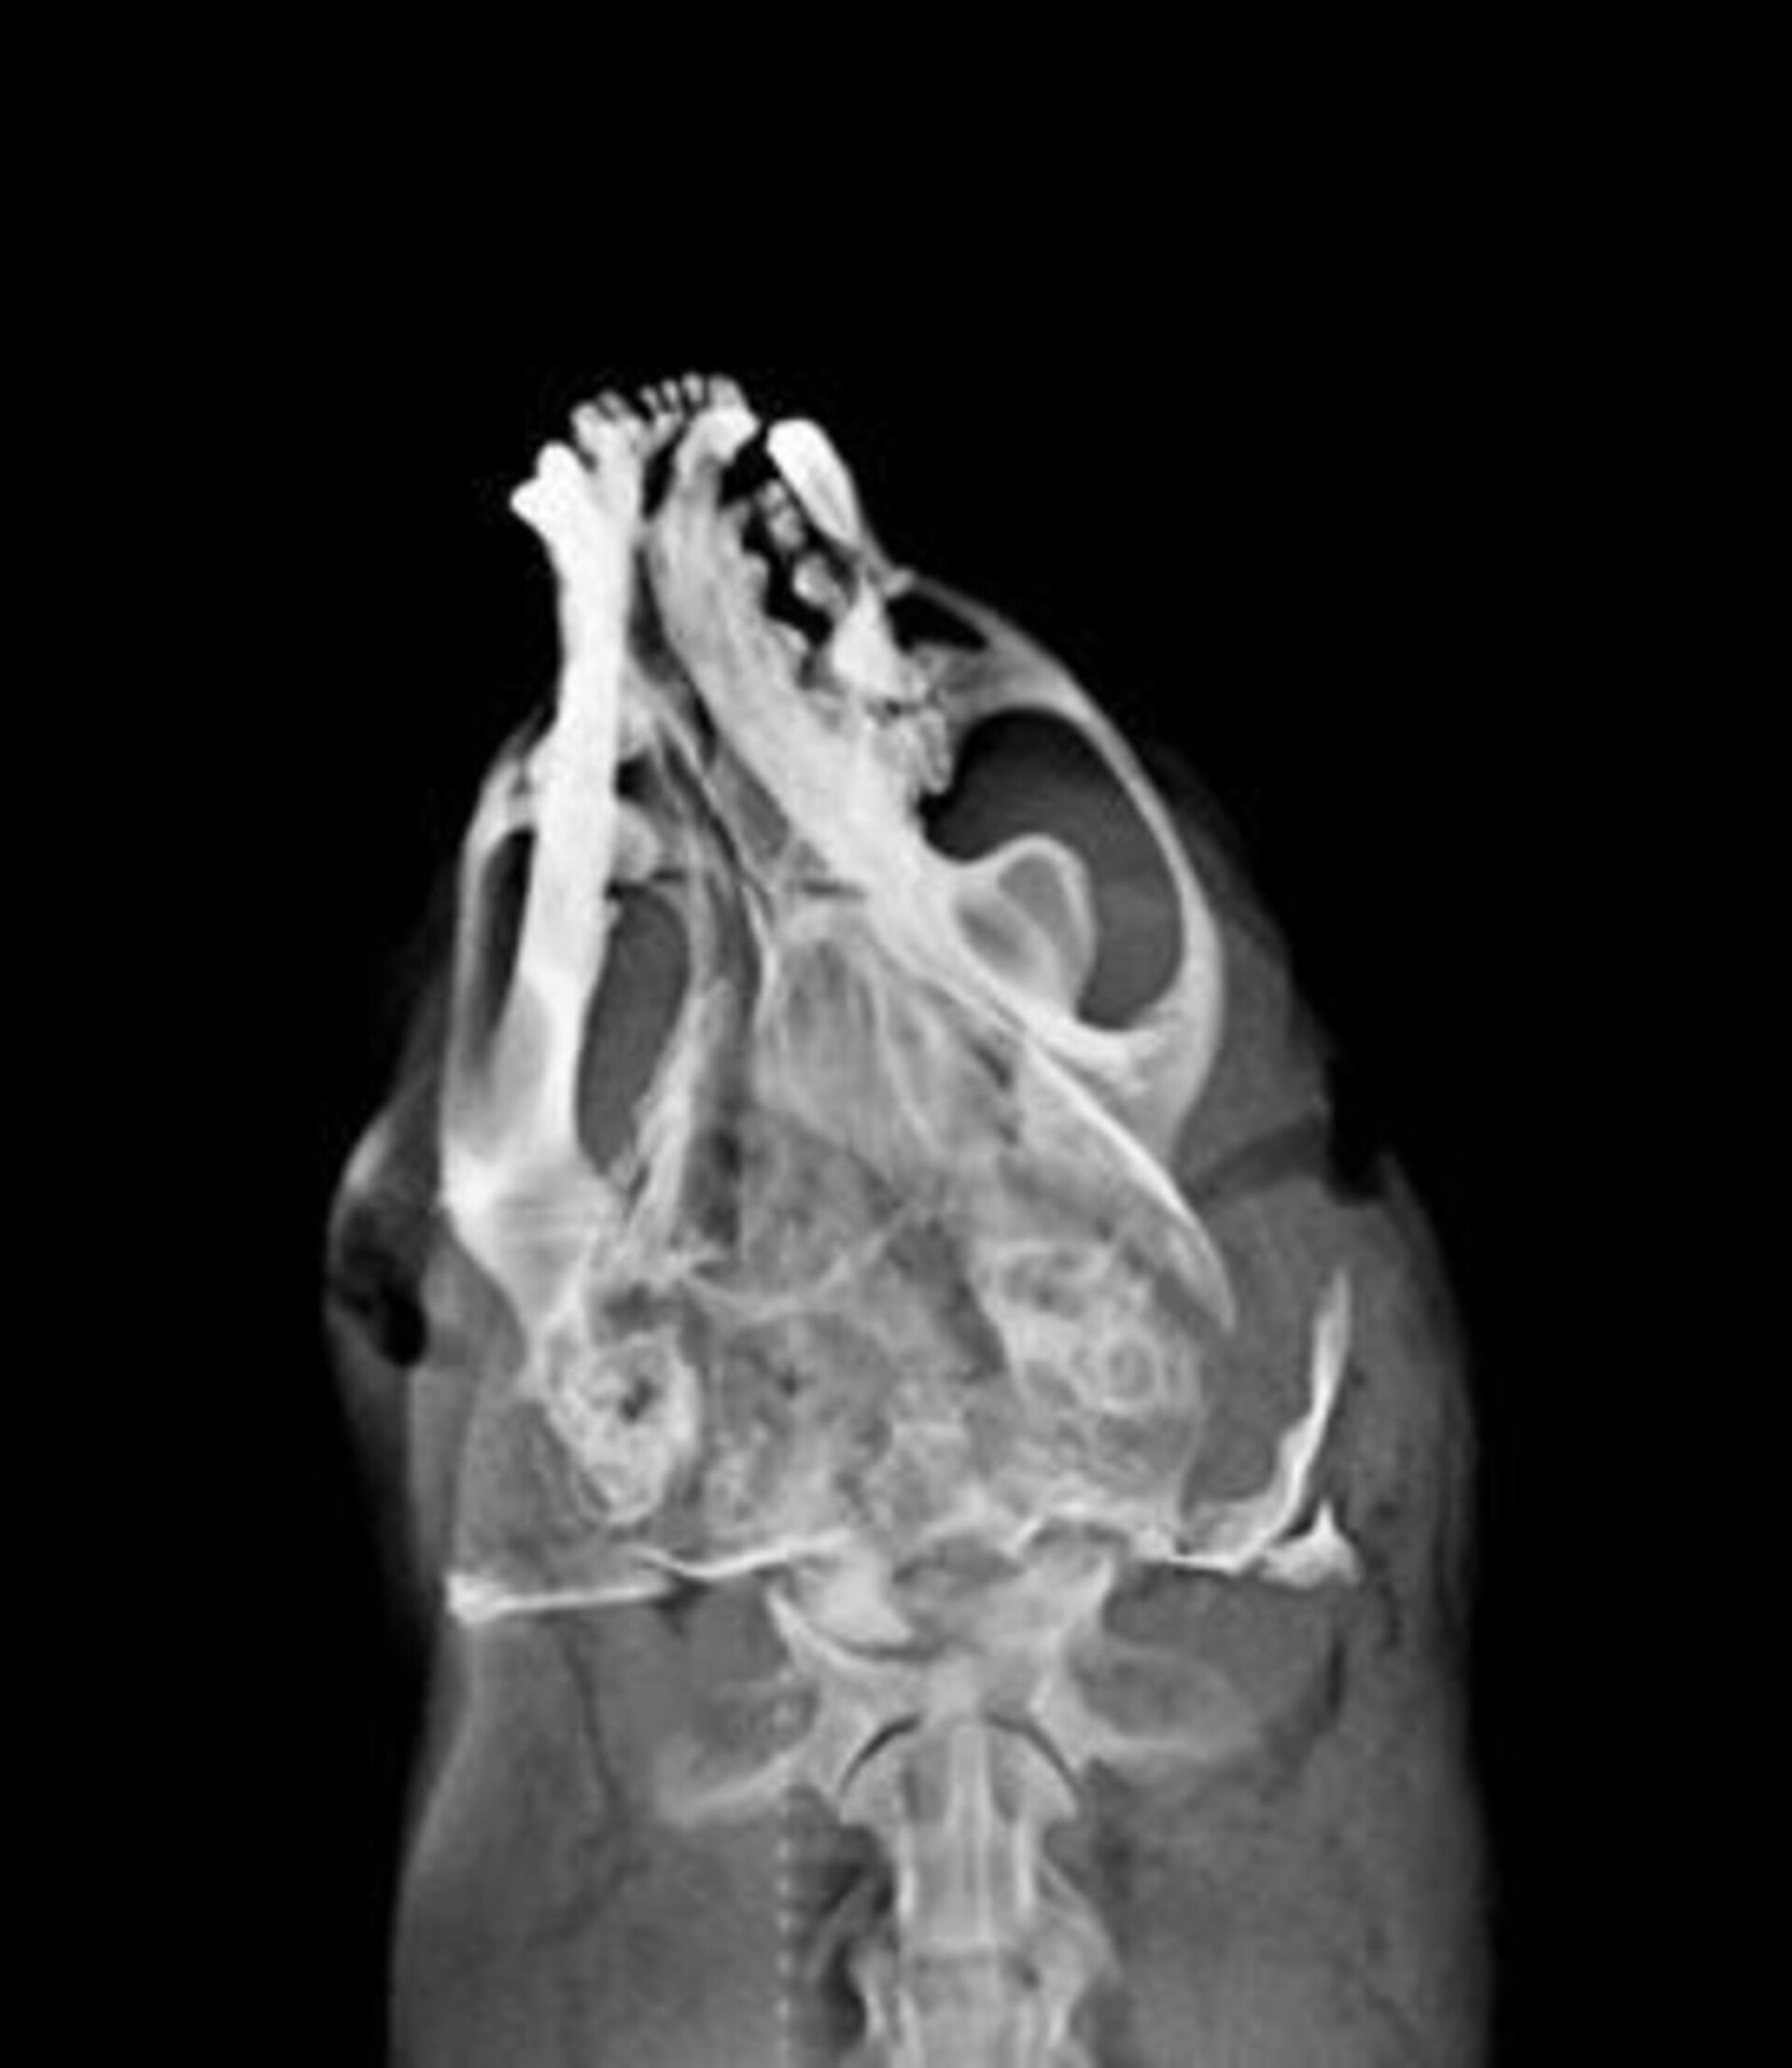

編號D105002水獺。成年雄性可見睪丸,體重5.95Kg,身長106cm、胸徑36.5cm,口鼻流大量鮮血,受理時仍為溫體但已無呼吸心跳。X光檢查頭骨粉碎性骨折、下頷骨骨折、肺前葉出血。死因判定為強烈外力撞擊頭部造成死亡。